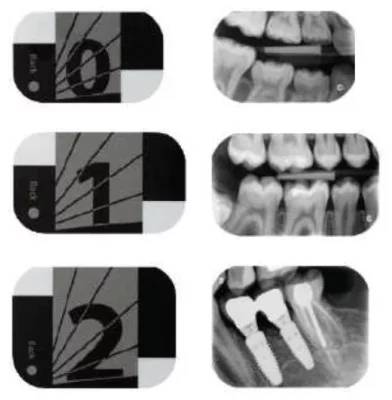

CS 7200 se dodává s fóliemi třech velikostí (0,1, 2), které spolu s reálným rozlišením 17 lp/mm zaručují pokrytí všech běžných intraorálních vyšetření. Snímky díky novému způsobu zpracování latentního obrazu a širokému expozičnímu rozsahu jsou ostré, s vyváženým kontrastem a nízkým šumem. Můžete si vybrat ze tří skenovacích režimů, podle toho, zda upřednostňujete rychlost nebo rozlišení. K dispozici jsou naprogramované filtry pro jednotlivé anatomické oblasti, které optimalizují zobrazení dané oblasti jediným kliknutím.